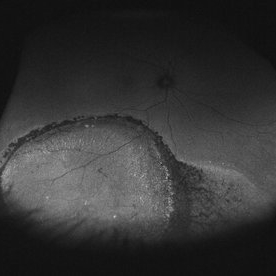

ERRODING-BUCKLE

Fundus photograph of a patient who underwent conventional retinal detachment surgery with an encircling element 25 years ago. The sponge visible under the retina has not changed in 5 years of follow up.

Photographer: Alex Frazer, Greenlane Clinical Center, Auckland, New Zealand

Condition/keywords: subretinal buckle